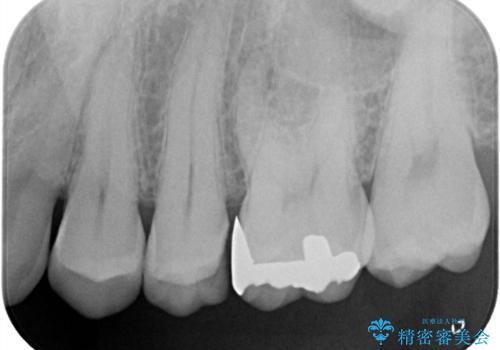

レントゲン検査で虫歯が認められました。

古い材料を除去後、その下に大きな虫歯が広がっていました。

神経の近くまで虫歯が広がっていたため、虫歯の除去後、神経を保護する材料をおきセラミックインレーで治療を行いました。